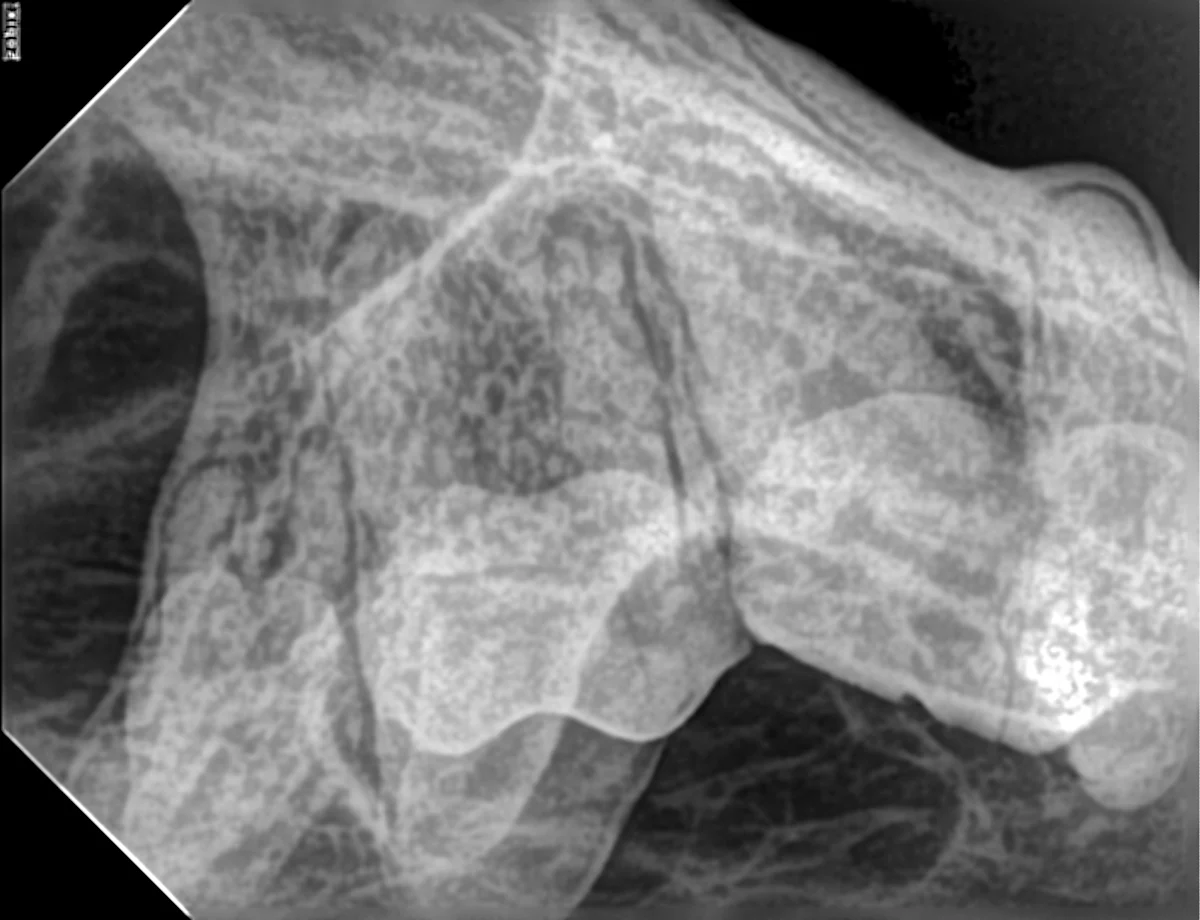

This author attempted the TOP technique on a dry-bone skull (Figure 2). An image that clearly showed the buccal roots of the first molar tooth (ie, 109) and second molar tooth (ie, 110) was obtained after 6 attempts in which the position of the sensor and angle of the tube head were adjusted (Figure 3).

Transorbital view of teeth 110, 109, and part of 108. Buccal roots of 110 and 109 and supporting bone are clearly visible and can be accurately evaluated.